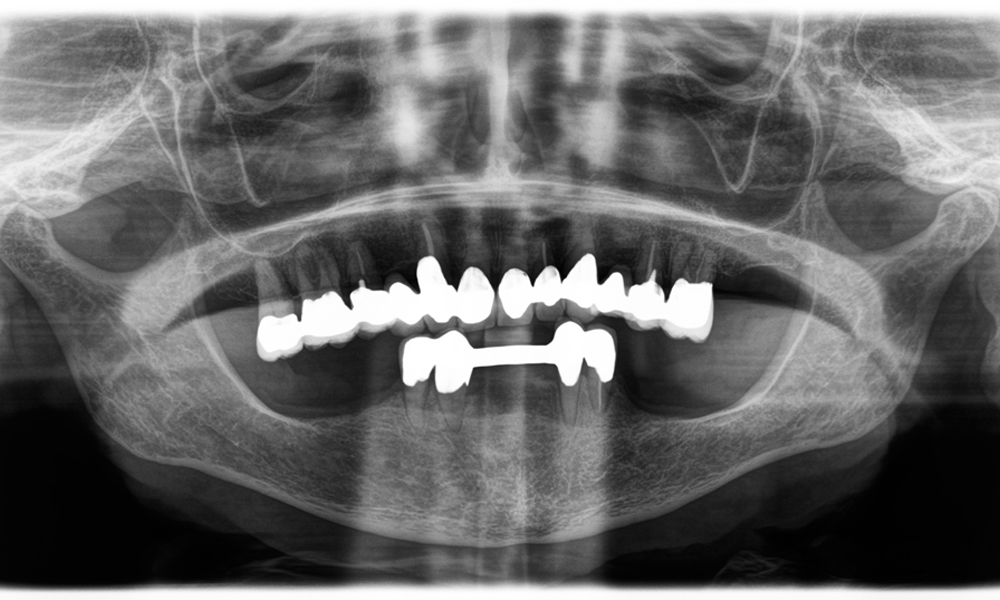

Un al doilea caz, care evidențiază capabilitățile clinice ale piesei Synea Power Edition, a implicat înlocuirea unei coroane din zirconiu deteriorate, la o pacientă în vârstă de 63 de ani. Pacienta prezenta o fațetă ciobită pe o coroană din zirconiu veche de 20 de ani, pe primul molar (#6). În ciuda localizării posterioare, pacienta considera defectul deranjant și a solicitat o nouă restaurare.

Piesa Power Edition a permis secționarea precisă, cuplul crescut și răcirea îmbunătățită contribuind la îndepărtarea controlată a coroanei, fără pierderi semnificative de material. Sistemul de prindere și cuplul îmbunătățit s-au dovedit esențiale în acest proces.